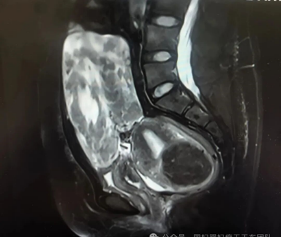

来自外省的李女士,体型偏肥胖,近两年发现子宫肌瘤增大明显并引起了严重的压迫症状。磁共振检查提示多发性子宫肌瘤,合并左侧宫旁阔韧带肌瘤伴变性可能,其最长径达到20多厘米。同时,既往有剖宫产史、右卵巢子宫内膜异位囊肿剥除术史,存在的盆腹腔粘连均使手术难度进一步加大。